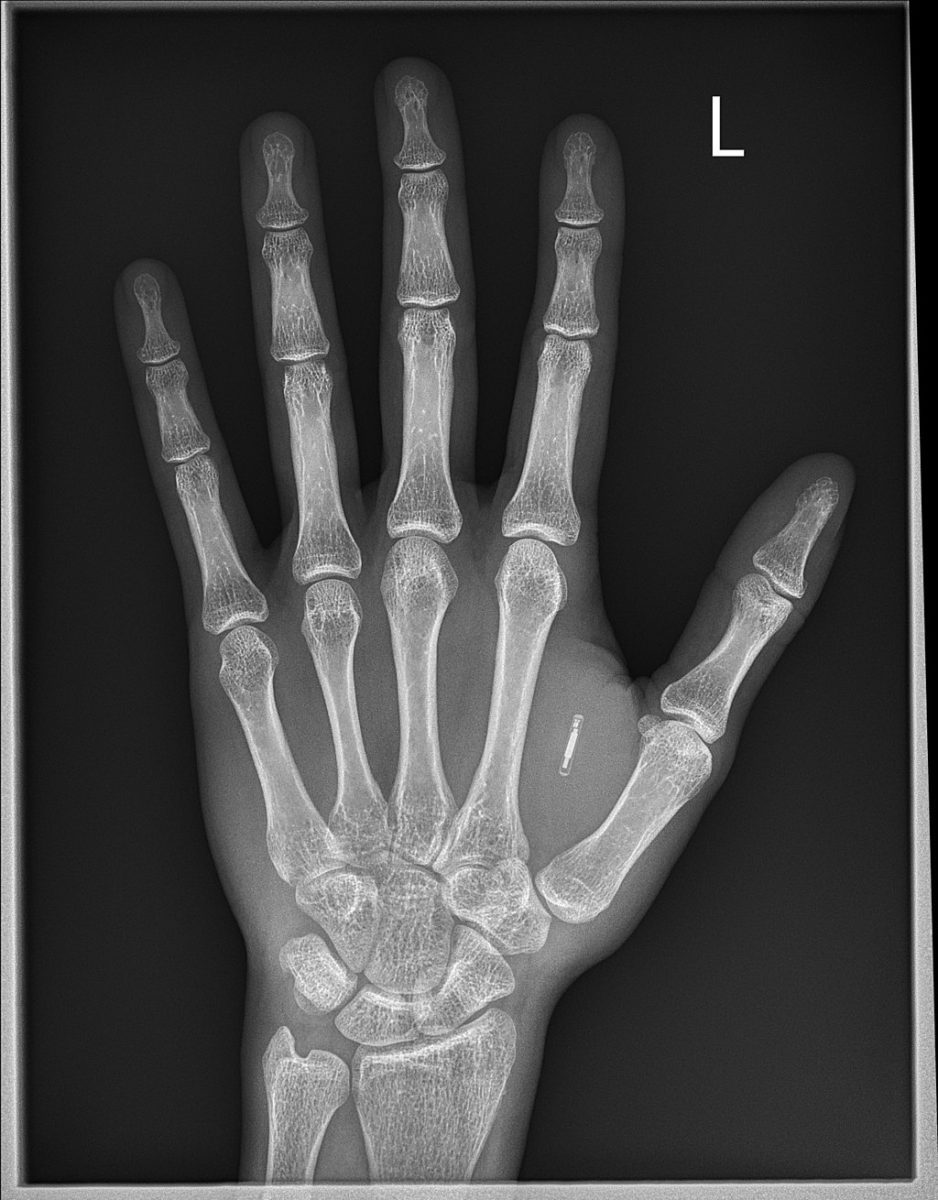

Valamint a kezünkbe épített pici RFID mikrochipekkel nyithatjuk az ajtókat, és működtethetjük a fénymásolót.

Ahogy azt a wisconsini Three Square Market cég ötven alkalmazottja már 2017-ben kipróbálhatta (az újszerű ötlet, hogy a dolgozókba chipet ültessenek, a cégtől származott, de a jelentkezés önkéntes alapon zajlott). A testünk viszont egyúttal információkat sugárzó antennává válik, és az adásba belehallgathatnak idegenek is. Feltéve, hogy vezeték nélküli rendszerrel működik. A B terv (vagyis inkább A), vezetékek alkalmazása a szervezetünkben is kockázatos: a biokémiai reakciók rongálják a huzalok bevonatát, így például egy agyba ültetett chip esetében kétséges a hosszútávú használat kimenete. Ez az egyik dilemmája a Testek Internetének.